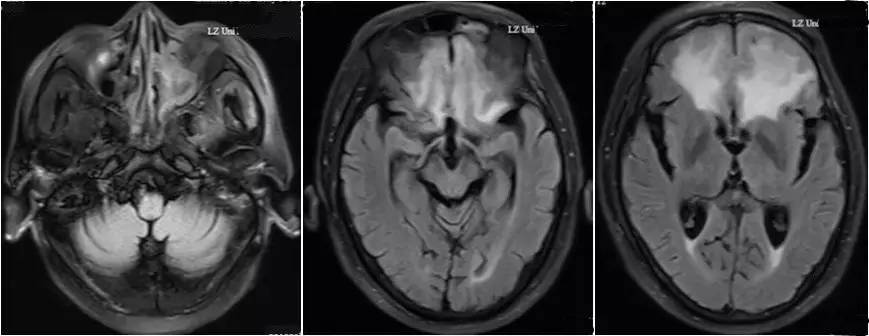

▼患者影像资料(2016-3-4)

复习病史,患者2013-7鼻内镜鼻腔肿物切除术,病理高分化腺癌,术后行同期放化疗,鼻腔局部照射65.72Gy/31f;2015-7出现前组脑神经损害症状体征,影像检查提示鼻腔及筛窦、额窦肿物,伴前颅底额叶异常强化及周围水肿,局部脑膜增厚、强化,颅底骨质不连续,考虑复发伴放射性改变;经鼻腔再次活检证实为复发;给予对症治疗症状加重,遂行PET/CT提示筛窦、双侧额叶、大脑镰、左侧眶周、海绵窦代谢增高;局部行射波刀治疗35Gy/6f,具体不详;疗后症状无明显缓解。首先双侧额叶改变MRI不能区别放射性脑坏死和肿瘤复发,可考虑进一步MRS、PWI、DWI成像提供更多的信息鉴别两者;倾向于肿瘤复发可能性大,原因如下:病变范围可能远远超出照射野;距放疗时间较短,文献报道一般放射性脑坏死中位发生时间约6年;颅底骨质破坏伴代谢增高,且与鼻腔、筛窦、左眶、海绵窦代谢一致。当然也不排除同时合并放射性损害,毕竟同时行化疗,可能较单纯放疗反应重。关于是否再行放疗改善症状,取决于前2次放疗的评价,看危及器官尤其是脑干、健侧视神经是否还能耐受;可使用卡马西平0.1、Tid,可能减轻神经痛症状;对症支持治疗方面适当应用激素、甘露醇等减轻脑水肿;也可考虑联合贝伐单抗;后续肿瘤治疗以化疗为主,请Z主任斟酌方案。